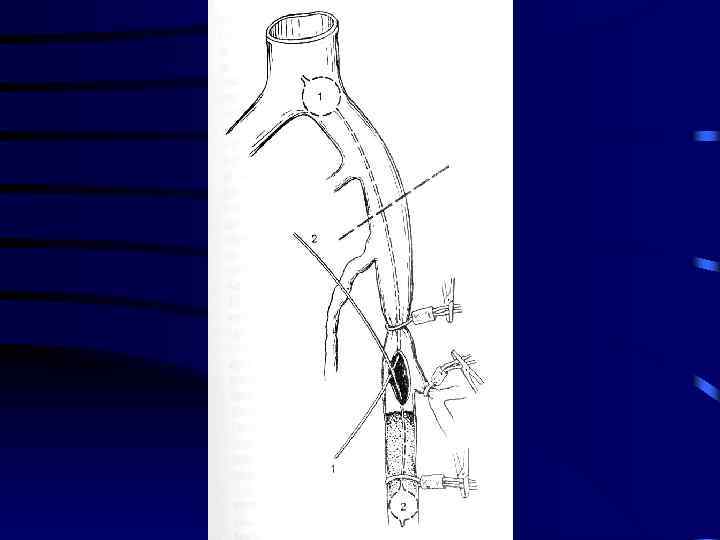

Лечение: 1. Консервативная терапия: a) Эластическое бинтование с возвышенным положением b) Гепарин c) Антибиотики d) Покой 5 -7 суток 2. При флотирующем или эмбологенном тромбозе хирургическое лечение: a) Установка Кава-Фильтра b) Пликация вен выше места тромба